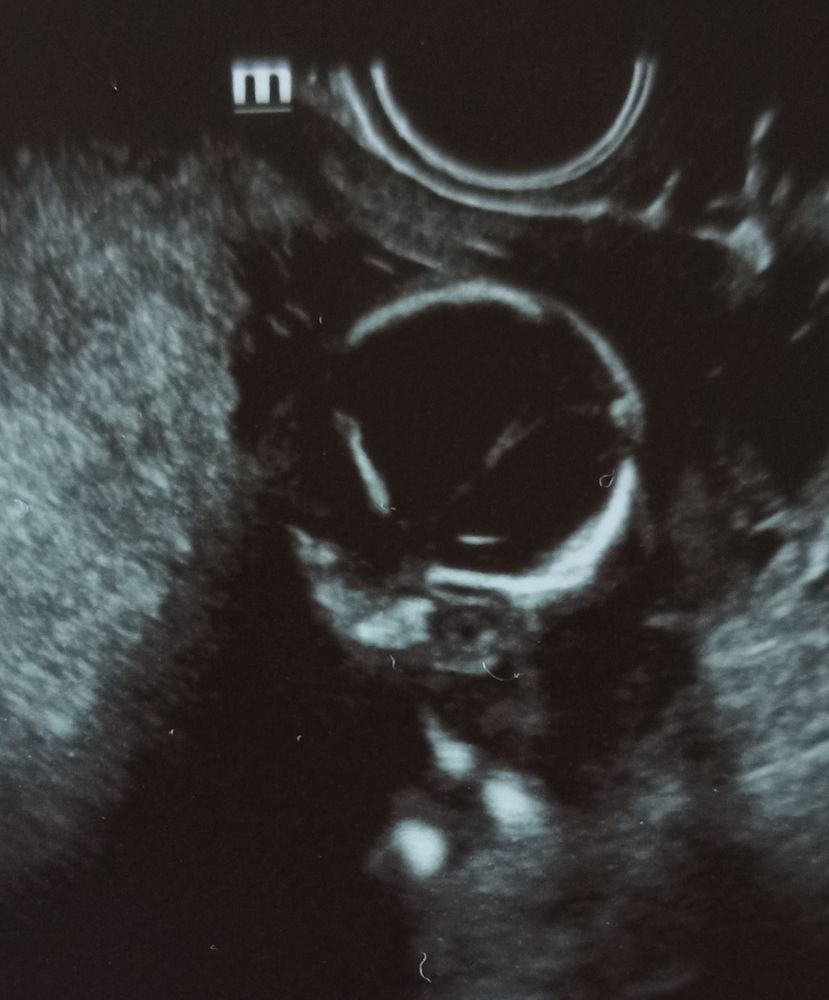

Единственное, что смутило, что костная часть спинки носа маловата - 3,3 мм на сроке 16 недель и 3 дня ( норма в 16-17 недель - от 3,6 мм). Я думаю, это не критично и НИПТ развеет все сомнения. Остальное всё в норме, соответствует сроку. Вес сыночка 166 грамм.

На фото открыл глазки:

Во - вторых, сегодня по УЗИ в 16+3 носовая кость маловата - 3,3 мм ( норма в 16-17 недель от 3,6 мм);